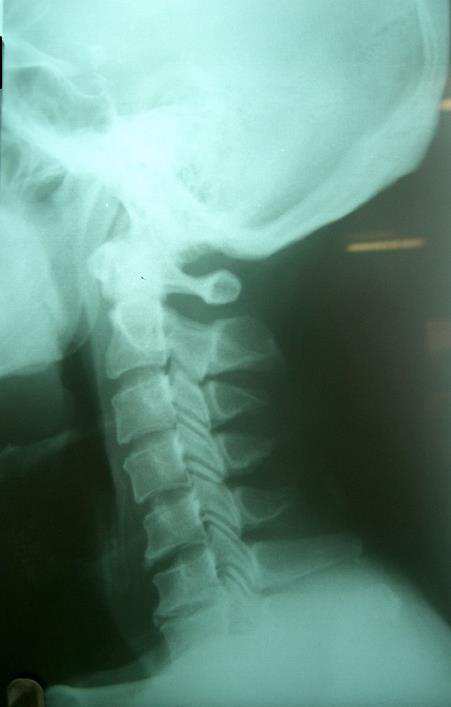

일자목과 디스크를 진단 받은 환자를 추나요법으로 치료한 사례

20대 여성이 목디스크로 인해 만성적인 목의 통증과 어깨 통증으로 내원하였으며 추나요법으로 호전된 치료사례

일자목으로 목의 통증을 호소하는 환자분으로 허리 역시 일자 허리 인데 같이 목이 아프다고 해서 목만 치료해서는 안되고 같이 치료해야 좋아질 수 있습니다.